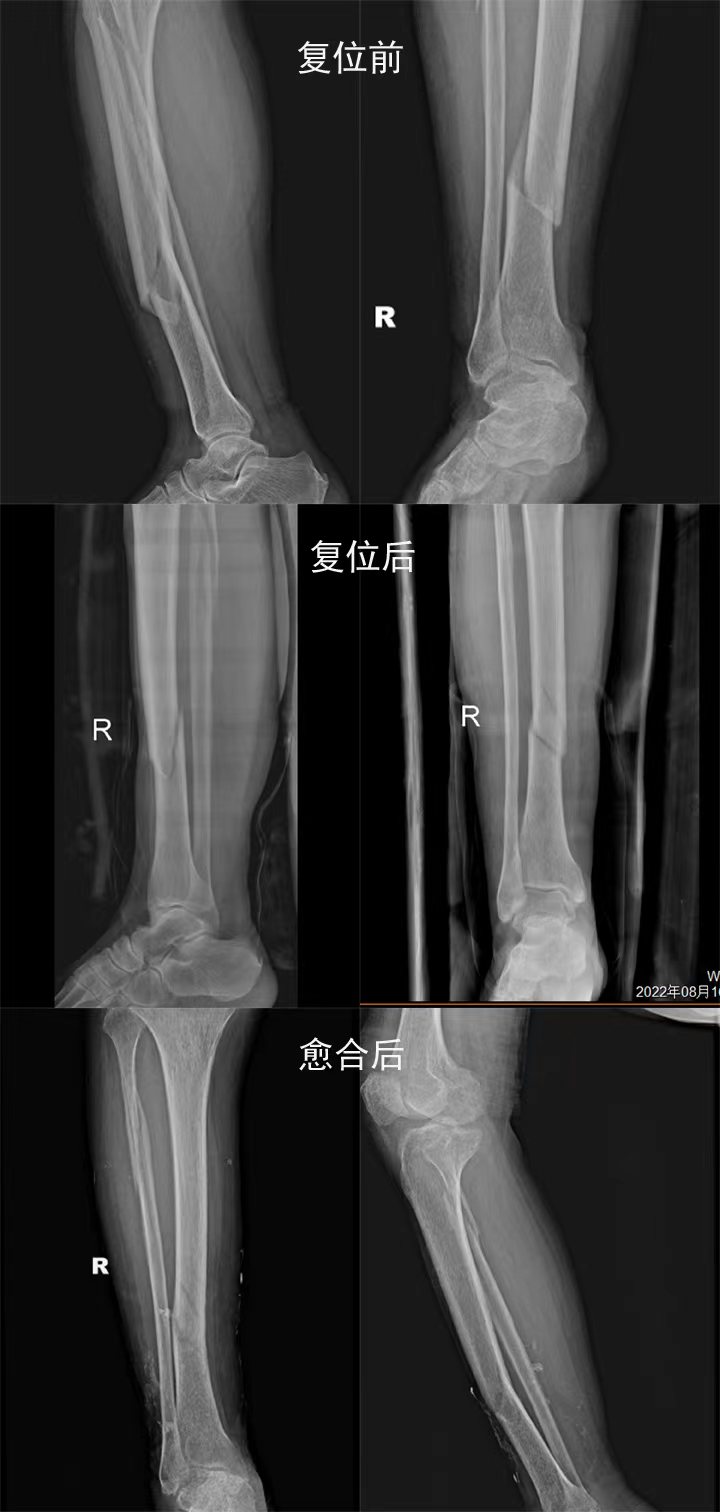

骨一科梁光兴主任正骨案例

老年女性患者,意外受伤,胫腓骨骨折,行手法复位,对位对线良好,愈后佳